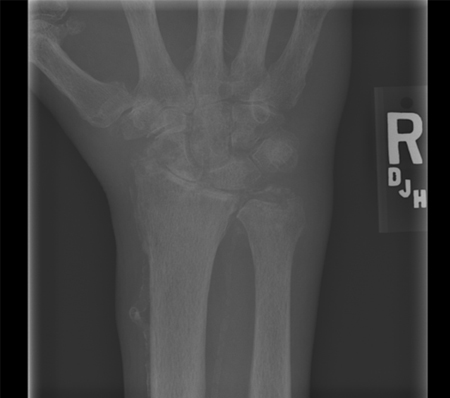

Plain x-rays of the affected joint can be helpful diagnostically.[46] Cartilage calcification can be seen in small joints, but patients with suspected polyarticular CPPD should have x-rays of the knees, pelvis, and wrist. These films have the highest likelihood of revealing radiographical cartilage calcification.[47] Plain x-rays can also rule out fractures, lytic bone lesions, and changes consistent with erosive rheumatoid arthritis. [Figure caption and citation for the preceding image starts]: Knee x-ray with linear calcific deposits of cartilage calcificationFrom the personal collection of Ann K. Rosenthal, MD [Citation ends].

[Figure caption and citation for the preceding image starts]: Wrist radiograph from a patient with chronic calcium pyrophosphate arthritis showing severe degenerative changesFrom the personal collection of Ann K. Rosenthal, MD [Citation ends].